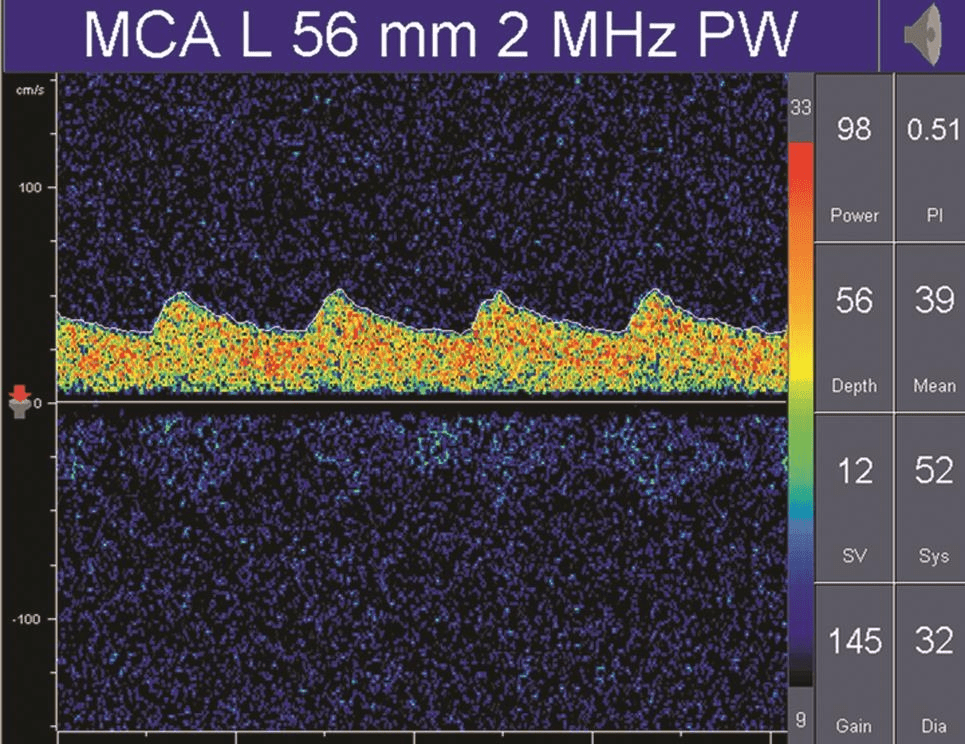

在病理情況下,低阻力頻譜可見于動靜脈畸形供血動脈、大動脈嚴(yán)重狹窄或閉塞后遠(yuǎn)端灌注明顯不足的血管內(nèi)血流及開放的側(cè)支循環(huán)(詳情見下圖);

TCD多普勒TCD低阻力血流頻譜

可見,除血流速度和血流方向之外,PI值是分析TCD血流頻譜的另一個非常重要的參數(shù)。